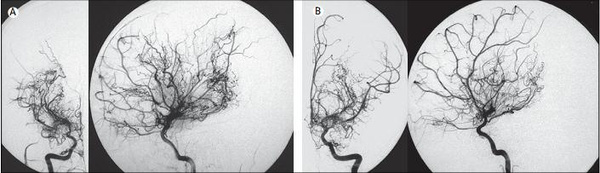

目前, DSA仍是诊断Moyamoya病的金标准。磁共振成像(MRI)和磁共振血管造影(MRA)的应用为Moyamoya病的病理血管检出提供了一种非创伤性方法。不少学者提出MRI和MRA两者结合可完成诊断的观点。应用缩短扫描时间的高分辨率turboMRA诊断Moyamoya病的敏感性和特异性可分别高达98%及100%,已有学者通过建立依据MRA结果且与Suzuki分级方式契合良好的分级系统,但MRA也有其局限性,如空间分辨率低,有夸大血管闭塞及狭窄-闭塞变化的趋向,在拟行手术治疗时,为了解精确解剖、病变血管狭窄程度和除外一些危险因素, DSA是必需的。一旦诊断确定,可结合使用Doppler超声、氙增强CT(Xe-CT)、正电子发射体层成像(PET)、单光子发射体层成像(SPCET)、弥散加权成像(DWI)、灌注加权成像(PWI)和磁共振波谱分析(MRS)等方式来评估患者脑区域血供、代谢分布,用以帮助决定治疗方式,评估手术效果。